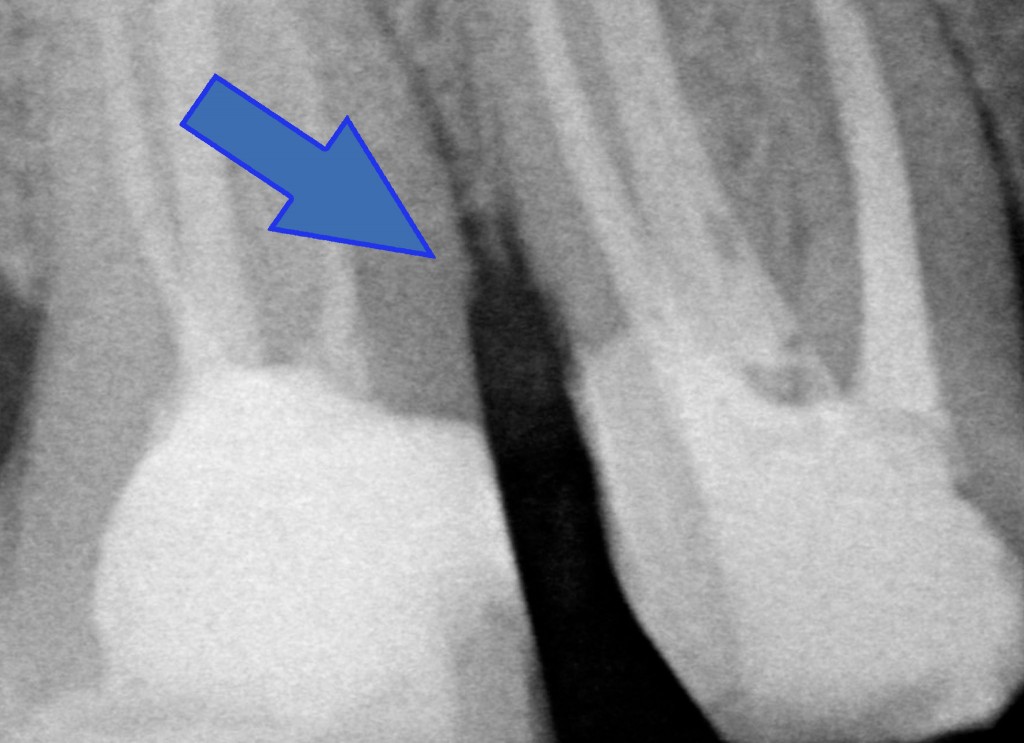

“Hei hei guarda un po’ lì cosa ha combinato questo?! Una tacca sul dente dietro!!”

Beh caro amico, la fresa tra i due denti ci deve passare e se le due radici sono troppo vicine bisogna creare lo spazio per una papilla interdentale sana e non sofferente, dove poter mettere un filo retrattore (anzi due) alla presa dell’impronta. Quindi sì, lo ammetto: una tacca di qua e una tacca di là!

PS: l’allungamento di corona clinica non vuol dire aprire la papilla fresare un po’ di osso interprossimale e chiudere! Quello tecnicamente si chiama creare un difetto parodontale iatrogeno.